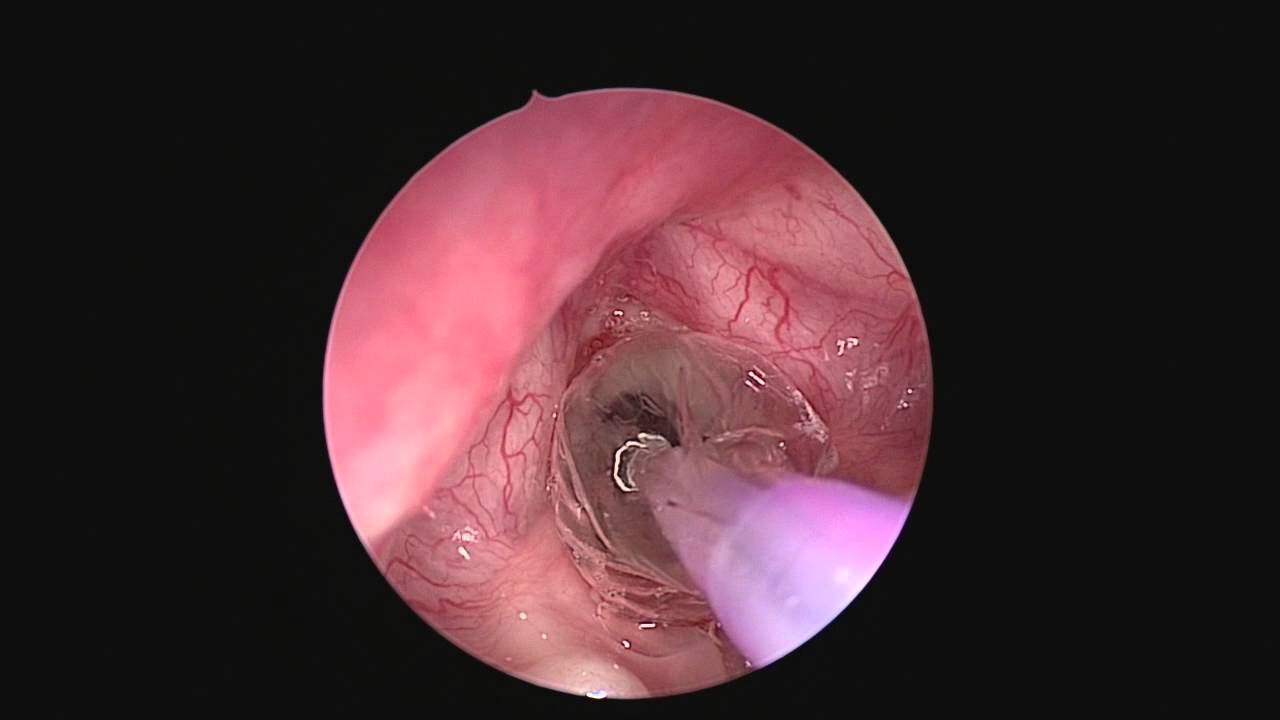

КТ органов грудной клетки. Стеноз правого главного бронха за счет мягкотканного образования в его просвете.

Решающее значение в диагностике стеноза трахеи и бронхов принадлежит эндоскопии дыхательных путей – трахеоскопии, бронхоскопии , в процессе которых есть возможность визуально подтвердить морфологические изменения трахеобронхиальной стенки, уточнить с помощью биопсии этиологию стеноза (рубцовая, опухолевая, туберкулезная). У больных с органическими стенозами трахеи и бронхов исследование ФВД ( спирометрия , пневмотахография ) имеет второстепенное значение (выявляются обструктивные нарушения), однако эти методы широко используются для подтверждения экспираторного стеноза.